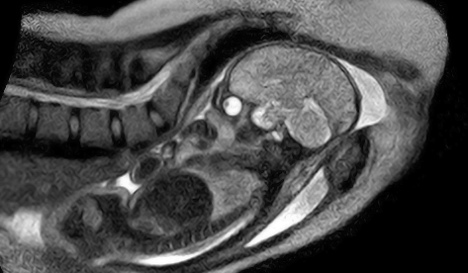

MRI Scan of Live Birth

Doctors at a hospital in Berlin created a MRI machine that allows a woman to give birth while being scanned. They hope that this machine will allow them to learn more about the mechanics of childbirth:

The new machine will enable the researchers to study in greater detail how the baby moves through the mother’s pelvis and down the birth canal – issues that have long been studied and debated. The hospital’s Institute for Radiology and Obstetrics Clinic will work closely together on the project.

Among other benefits, it should help researchers to understand why about 15 percent of pregnant women need a Caesarian section because the baby does not progress properly into the birth canal.